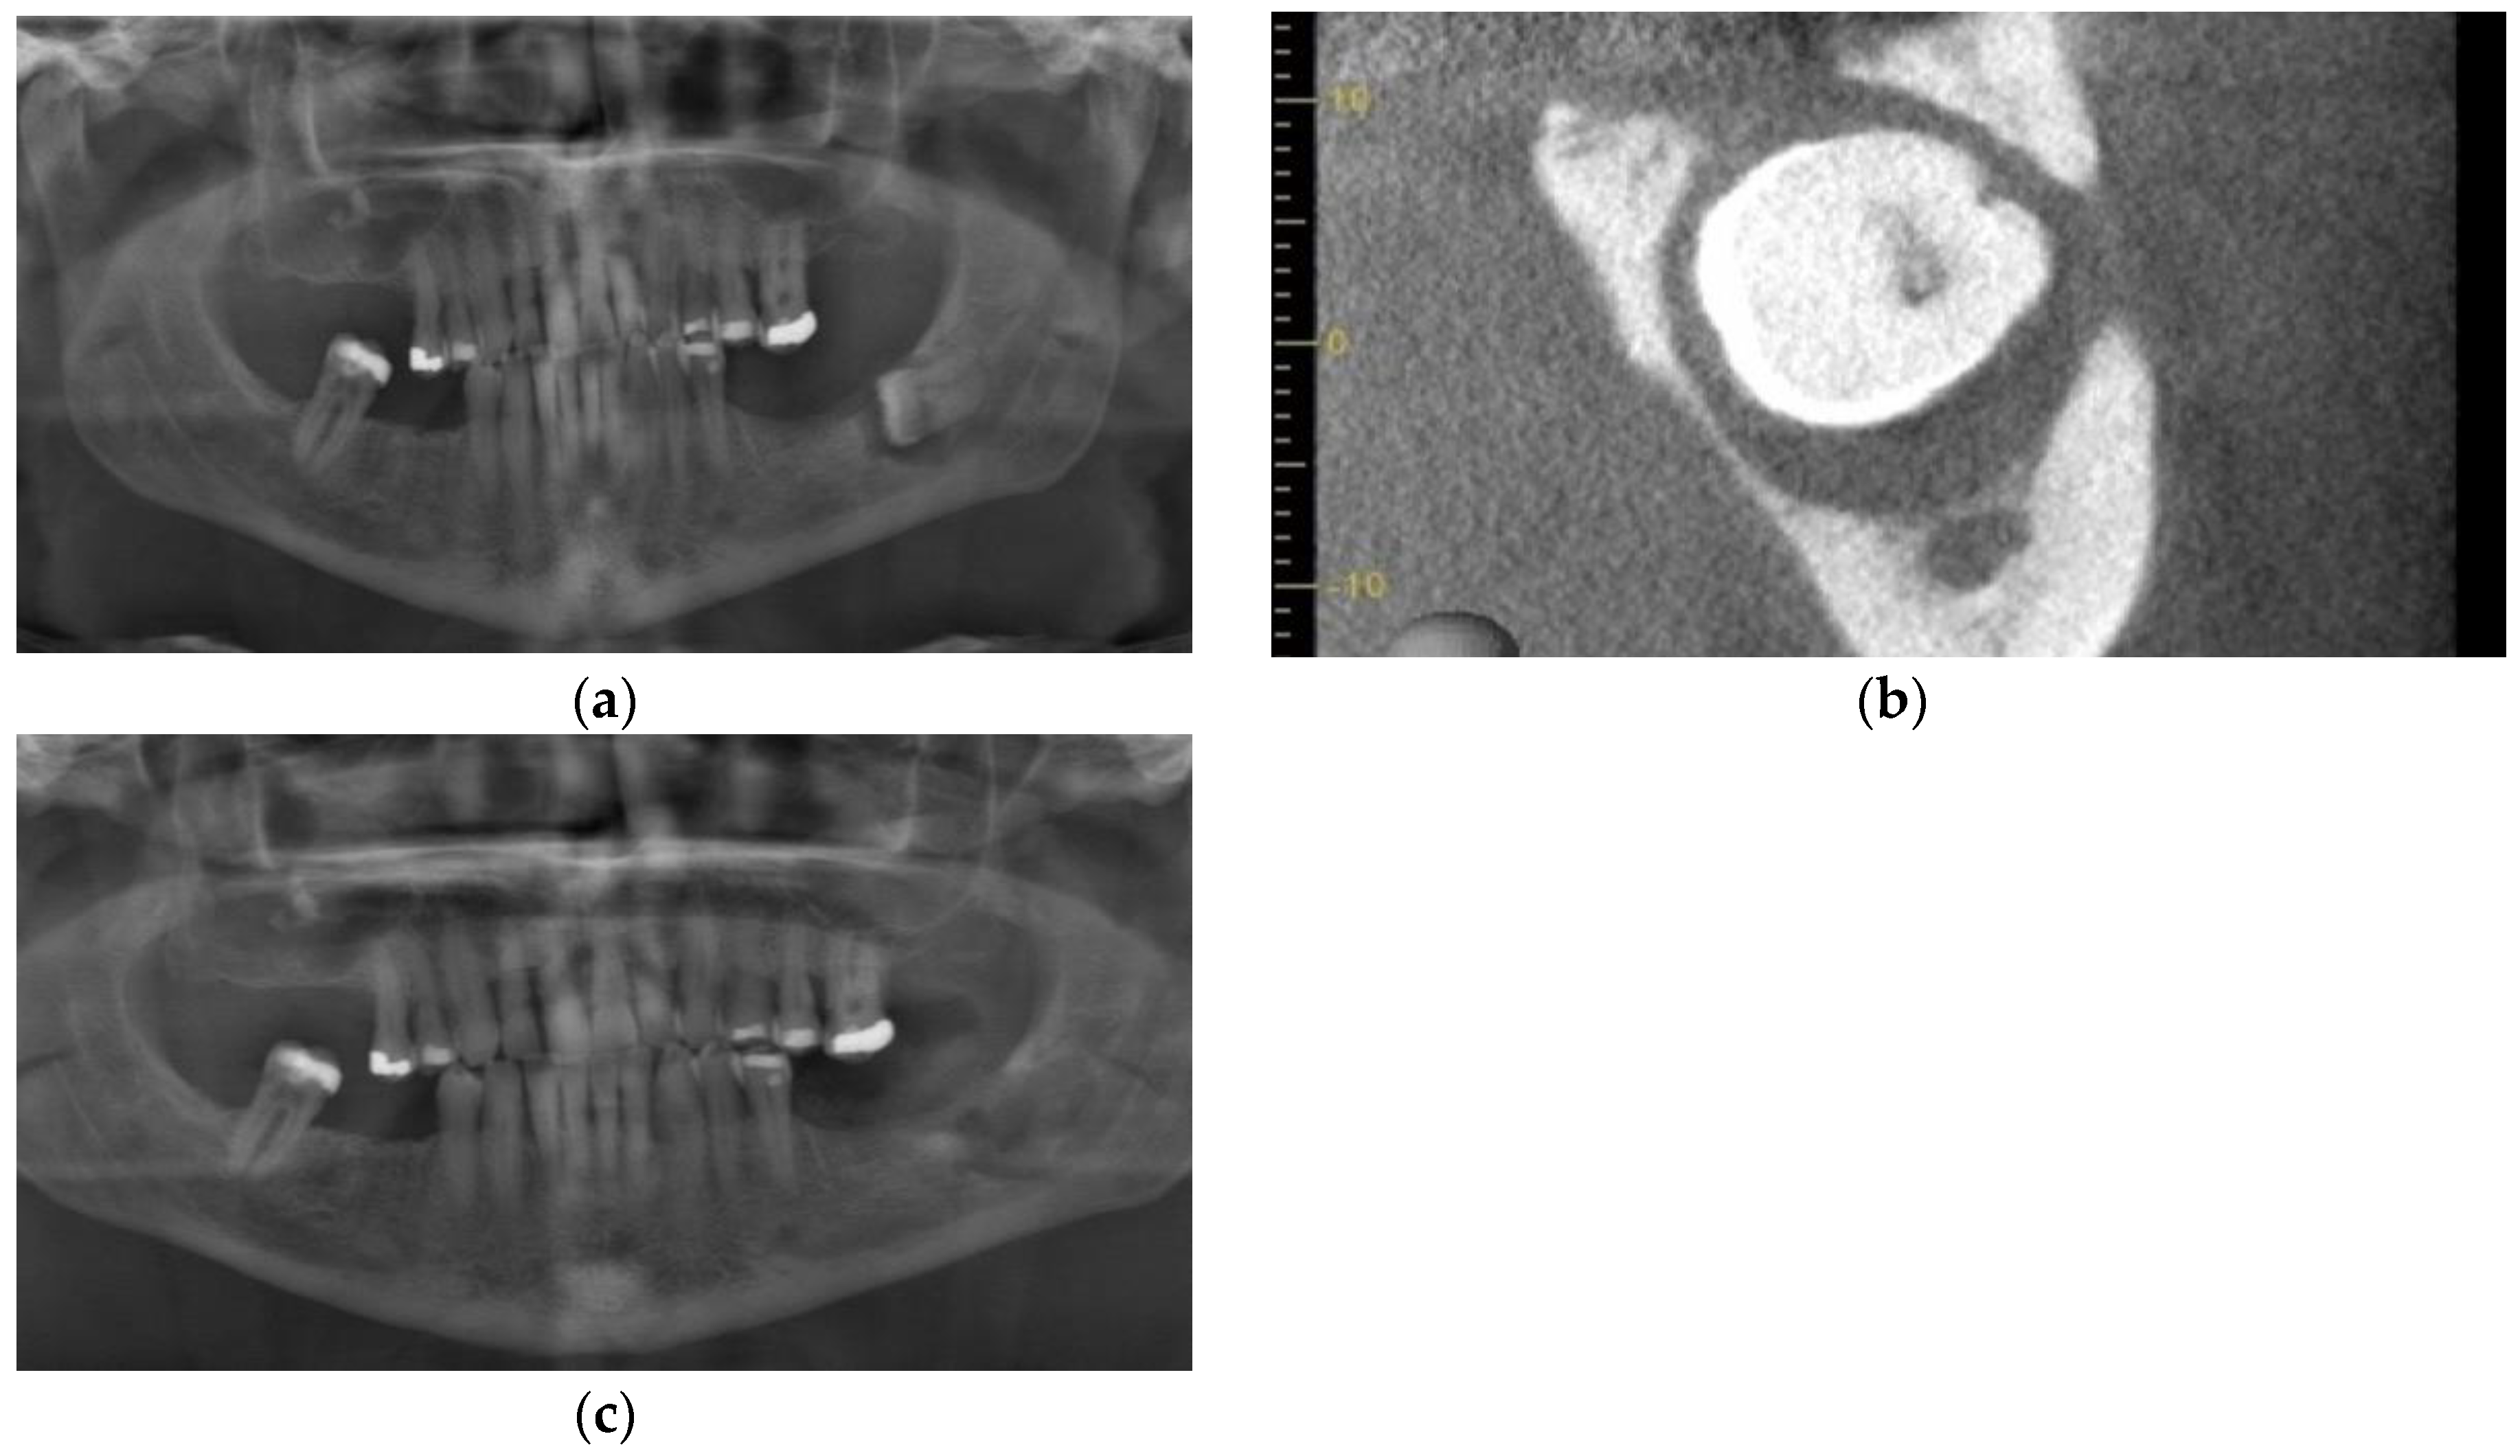

3.1. Case 1